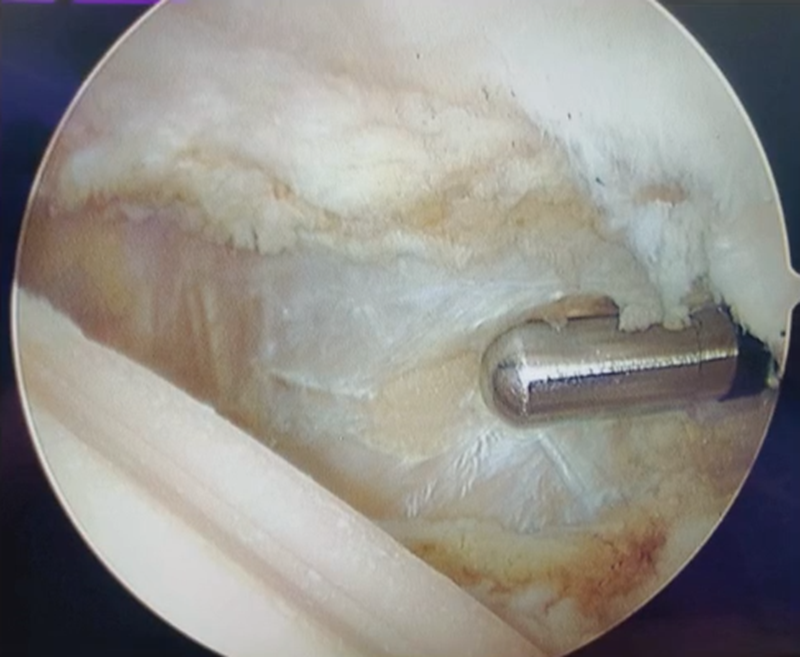

结合影像学检查,该患者不适合做关节置换,最终选择关节镜探查后,切开行髌骨成形术。

外侧入路切开,打开关节囊,术中可见大量骨赘,用咬骨钳去除。骨赘去除后,原来的Wiberg Ⅲ型髌骨恢复变为Wiberg Ⅱ型髌骨。